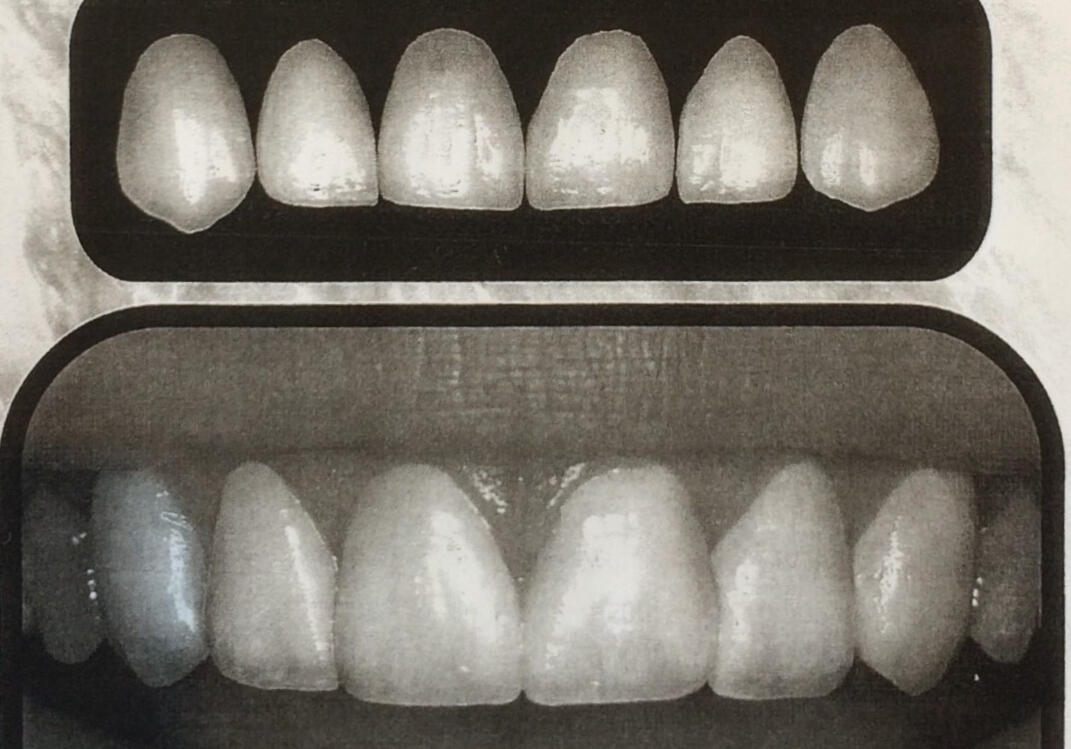

A veneer is a new front surface for a tooth, custom made from porcelain, composite or ultra-strong e.max glass ceramic. The strength of veneers can rival that of natural teeth to make beautiful, long lasting changes to your smile.With an accurate and thorough process, I can help you to achieve the smile you want, regardless of your staring point.

ConsultSpeak to me about what you are looking for: Decide on a colour, and gloss, texture and shape. Unsure? I can show you what is possible and am happy to advise. Using several smile sets - like the one below - which follow classical proportions and - a well-balanced look is ensured. You are free to change your mind, once you see how it looks in your mouth.Moulds are taken, with X-rays, measurements and scans and to indicate the best options.

PreviewUsing the help of a lab and/or digitally, you will be able to see if you will be pleased with the planned changes.

3 Preparation AppointmentAt this appointment your teeth are delicately prepared and moulds taken. You are given aesthetic temporaries to wear until the final veneers are ready so you can still smile. In the next 2 weeks your veneers and crowns are custom made to order, closely following the shades and shapes chosen. They are returned to Thomas before your fitting appointment so Thomas can measure and check them for accuracy.

4 Fitting AppointmentYou attend for your fitting appointment. The veneers are tried in and only when you are happy are they fitted with permanent adhesive.

5 Review AppointmentA week later I will see you to make sure you are completely happy.LongevityTreatments on these upper teeth were done to protect them after heavy, longterm erosion.Thomas protected the teeth with beautifully strong glass ceramic crowns (shown below) after using the Dahl technique.Immediately after they were completed they were brighter, provided a better bite and better filled the gaps to support the shape of the gums.Even two years later, the above photo shows that gum health is excellent and the crowns are showing no wear.

Veneers can be made of ceramics or composites (plastics). Both can be successful based on expectations.Intelligent Smile Design

Many dentists offer veneers and crowns made to measure: What some call smile design. The true measure of any treatment undertaken should be its longevity. Not only how it looks the day it is finished.But in the years to come.

BACK

Treatments on these upper teeth were done to protect them after heavy, longterm erosion.Thomas protected the teeth with beautifully strong glass ceramic crowns (shown below) after using the Dahl technique.

Immediately after they were completed they were brighter, provided a better bite and better filled the gaps to support the shape of the gums.

Even two years later, the above photo shows that gum health is excellent and the crowns are showing no wear.The patient is extremely happy with the outcome. Read more about how Intelligent Smile Design works to protect teeth and let you put your best smile forward.